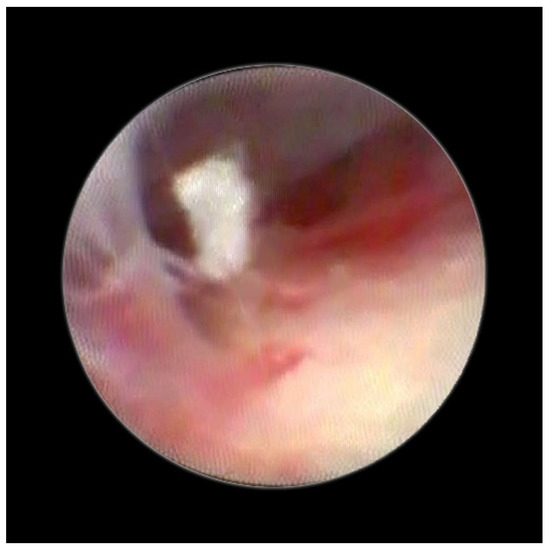

Figure 1 enables visualization of the composition of the normal dura and the other structure and directly indicates the absence of any median strand.

Figure 1. Normal dura in epiduroscopy.